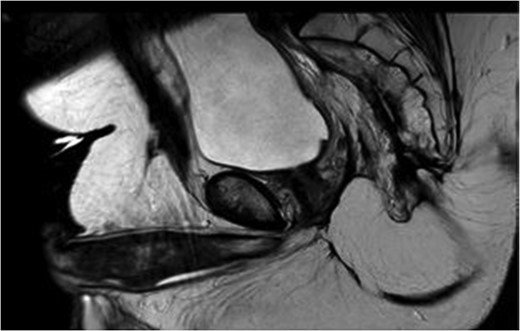

MRI pelvis. T2 waited axial image through lower pelvis through the large polypoid rectal tumour with T3 extension involving the CRM.